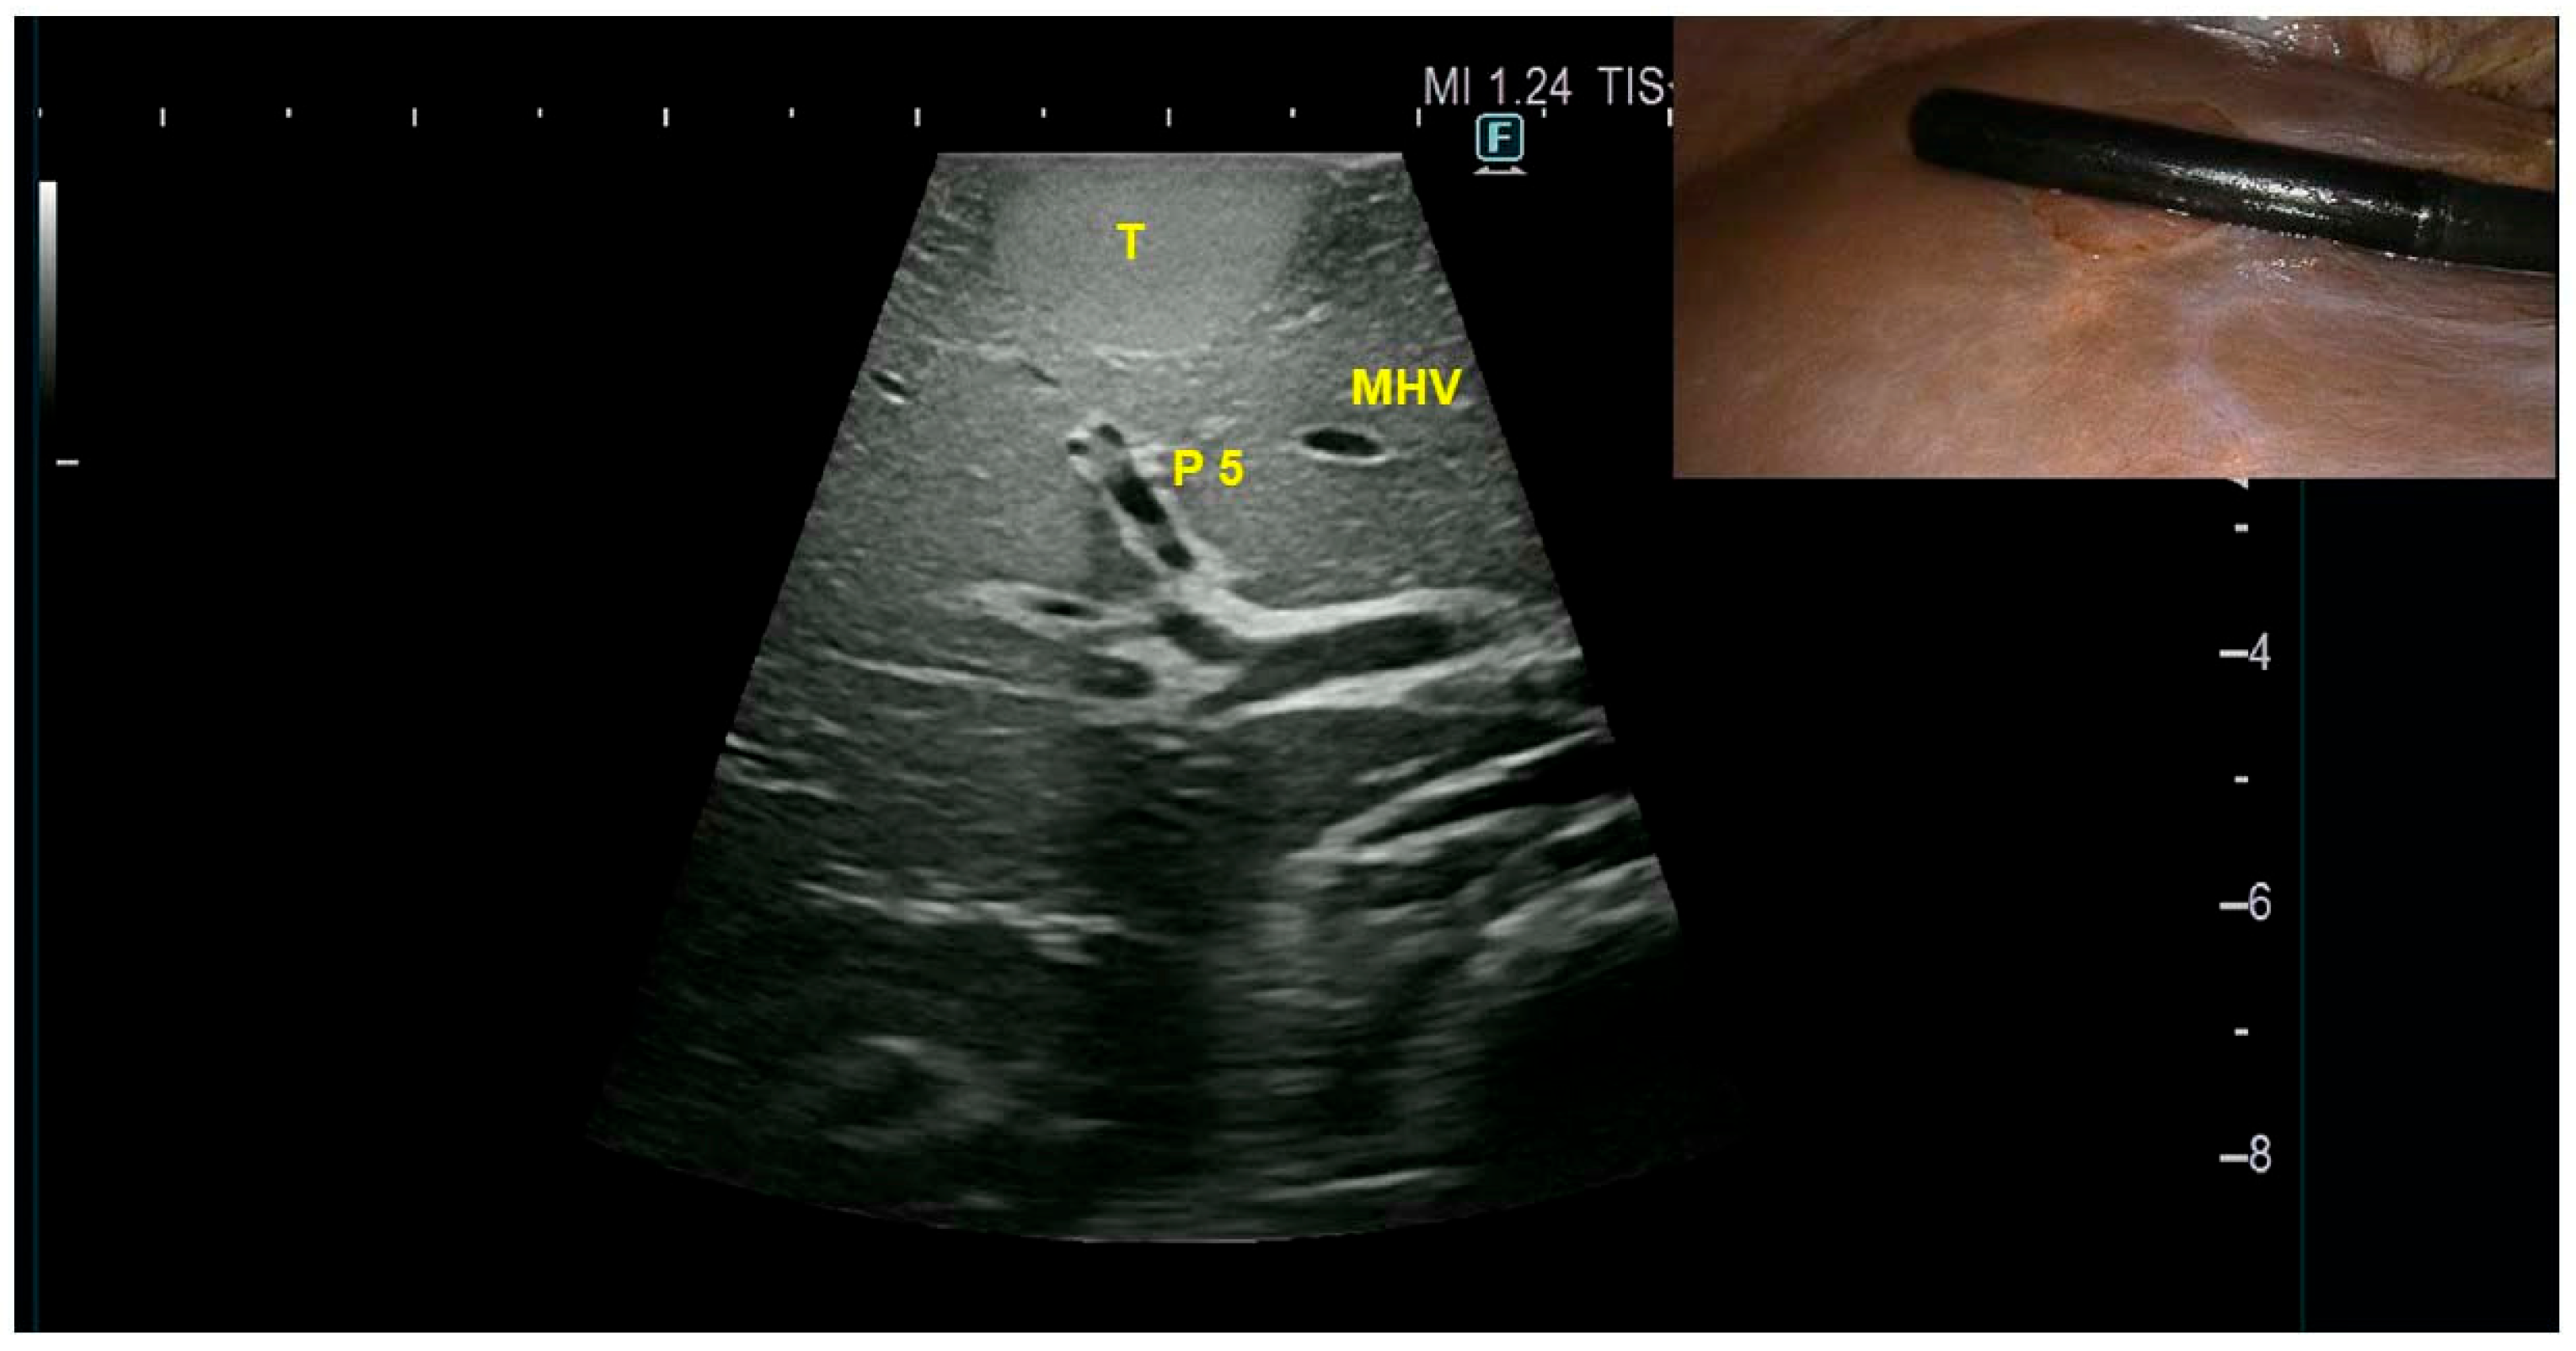

Case Presentation